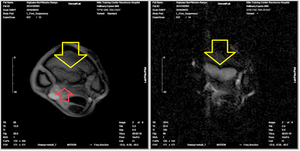

二つ目の症例は2歳の牡馬で、TC入厩後初めての追い切りで常歩でもわかる跛行を呈しました。管近位掌側に帯熱と触診痛を有したため、いわゆる深管(繋靱帯近位付着部炎)を疑ってレントゲン検査を実施しました。すると剥離骨折と思われる所見を認めましたが、不鮮明でした。そこで同部のMRIを実施したところ、不鮮明な像を認めた内側だけではなく、第3中手骨の外側まで広がる炎症像を認めました。本症例は、跛行の程度もなかなか改善しなかったため、MRI所見と合わせて1.5か月程度のやや長めな馬房内休養を提示しております。育成場では、しばしばこの深管といわれる病態に悩んでいる方も多いかと思います。本症例のように、レントゲン画像では不鮮明でも、MRIによって広範囲の炎症像が認められることはしばしばあります。

写真3 管近位のMRI横断画像

(左の中央に見える扇形の構造が第3中手骨。赤矢印が剥離骨折部位。黄色矢印は周囲の正常な第3中手骨と信号強度が異なり、骨炎症の範囲と考えられる。)